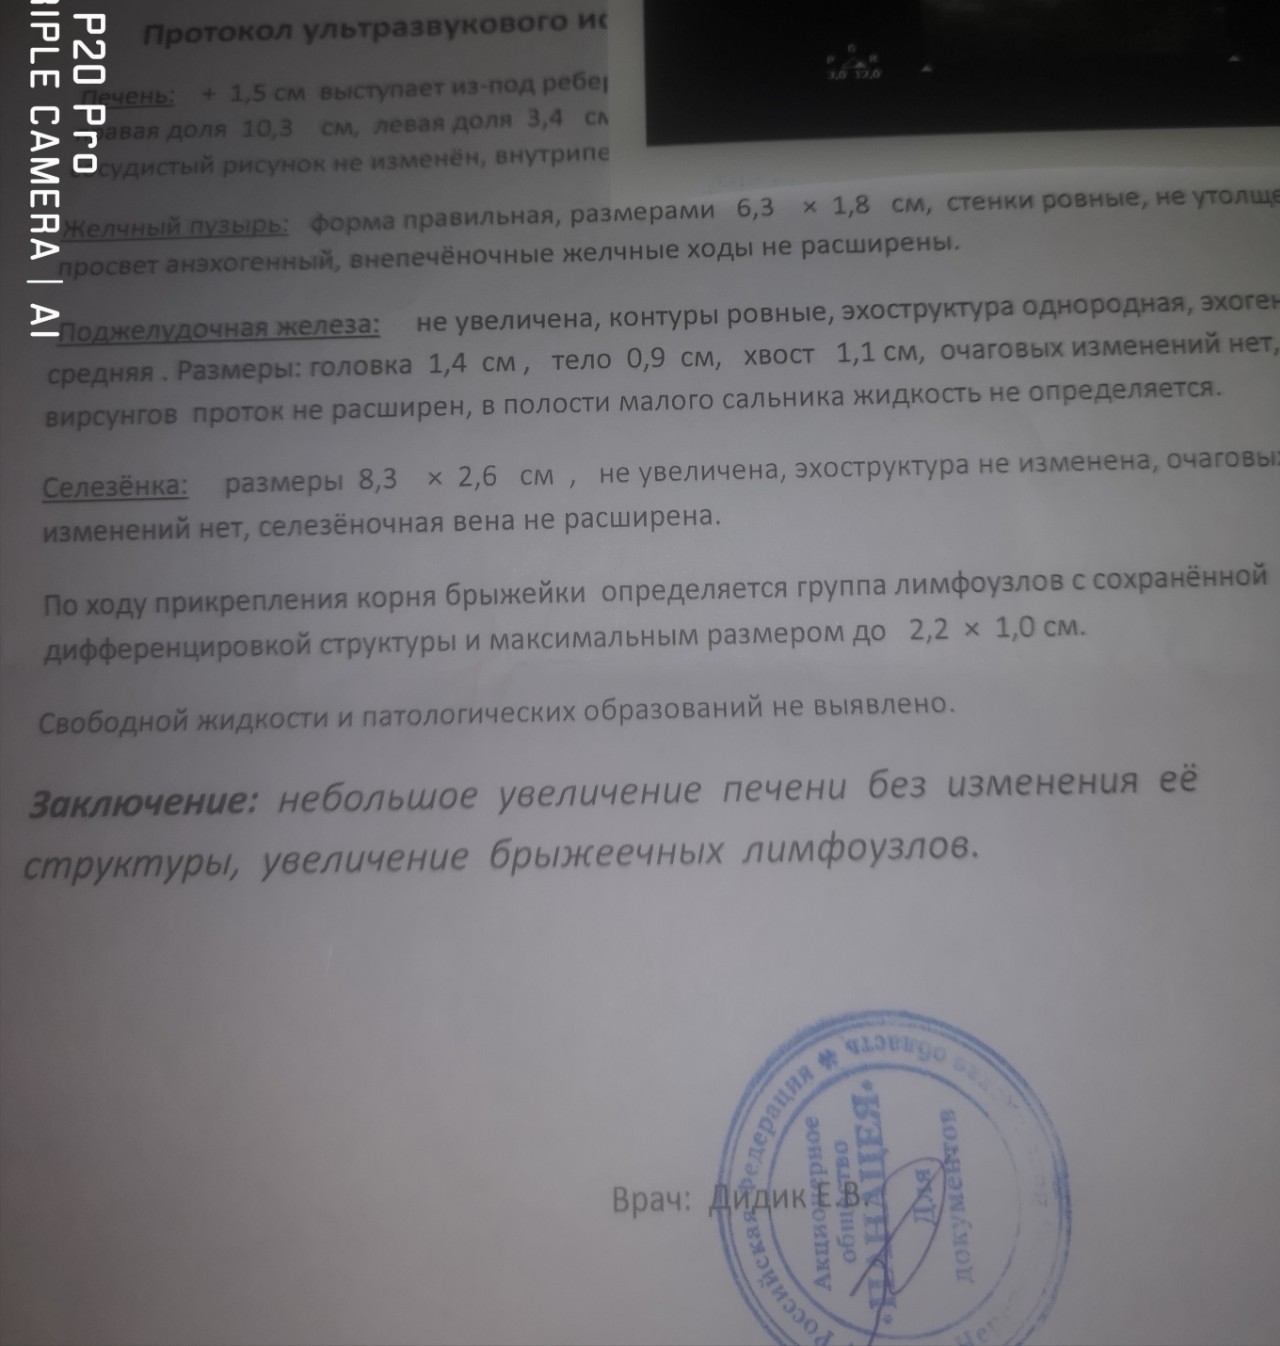

Мезентериальные лимфатические узлы: УЗИ и диагностика

Раздел: Лаборатория идей